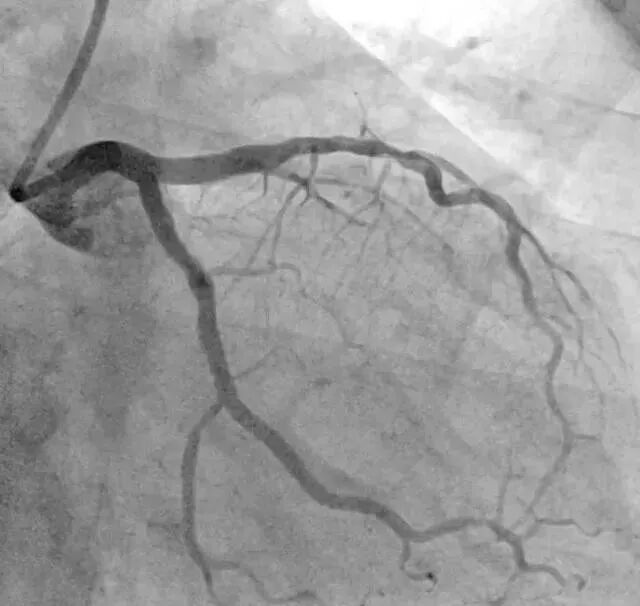

展露病变是造影的基本要求,体位角度不佳,可能会遗漏病变。现对蜘蛛位造影角度,做一探讨。常规角度多选 LAO 45 度、加足位 30 度。但病人心脏若垂位或横位,此角度可能就不适合,需要做一调整。